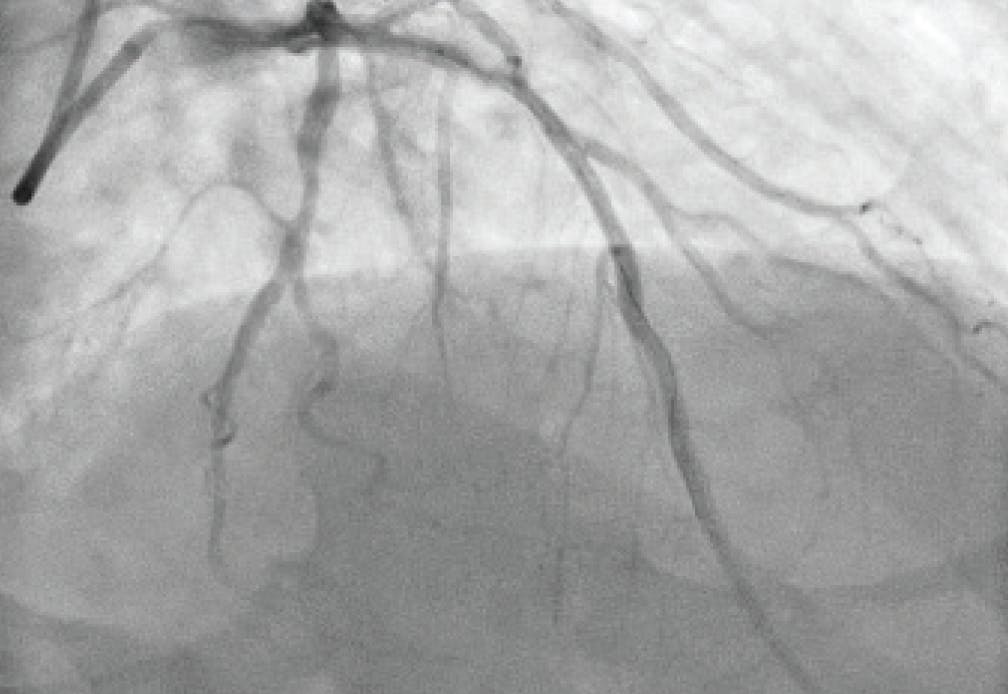

Figure 2. Initial angiogram of the right lobe.

INTERVENTION

After achieving wire access, the Lightning Flash 2.0 was inserted. While in “Gallop Mode,” the saddle clot burden and subsequently the left and right main PAs were aspirated. Once the algorithm returned to “Sampling Mode,” aspiration was turned off and angiograms were obtained to assess the progress. After 5 minutes of aspiration, reperfusion of the main PAs and distal branches was achieved (Figure 3, Figure 4, and Figure 5), with improvement in the patient’s vital signs and no device-related complications.

Figure 4. Postthrombectomy angiogram of the right lobe.